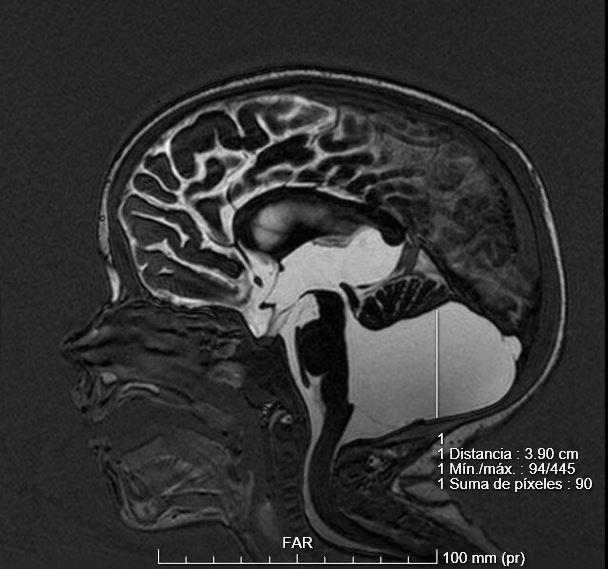

¿Por qué se caracteriza el síndrome de Dandy-Walker?: